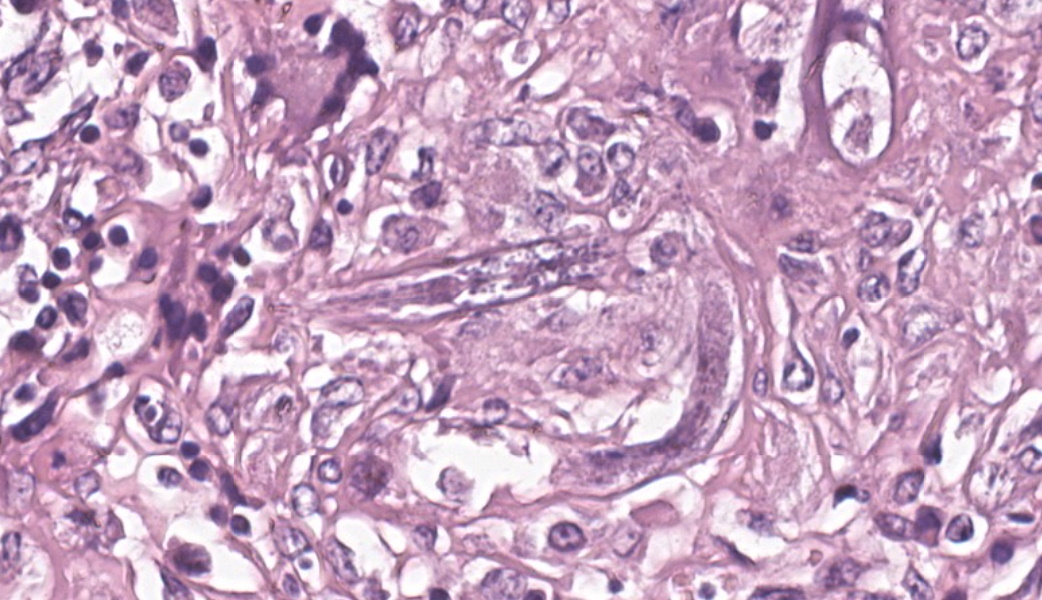

Kidneys: Multifocal to coalescent areas of loss of normal parenchyma with replacement by severe lymphohistioplasmocytic inflammatory infiltrate, with epithelioid macrophages, multinucleated giant cells, and large numbers of intralesional nematodes. Parasites were elongated, with aproximately 80 to 90 μm long (most of them fragmented), cylindrical, with sharp ends, covered by smooth cuticle, platimiarian musculature and an evident elongated and central rhabditiform esophagus, occupying the initial third of the body (morphology consistent with Halicephalobus gingivalis). Associated with these lesions there were also fibroplasia, necrosis, vasculitis and the remaining renal tubules were dilated and filled with macrophages, neutrophils, cellular debris, and numerous sections of H. gingivalis.

Kidneys: multifocal to coalescent, severe, chronic, granulomatous nephritis associated to intralesional nematodes compatible with Halicephalobus gingivalis and multifocal, severe, vasculitis, horse.

Kidney: Nephritis, granulomatous, chronic-active, multifocal to coalescing, severe, with adult and larval rhabditid nematodes and eggs.